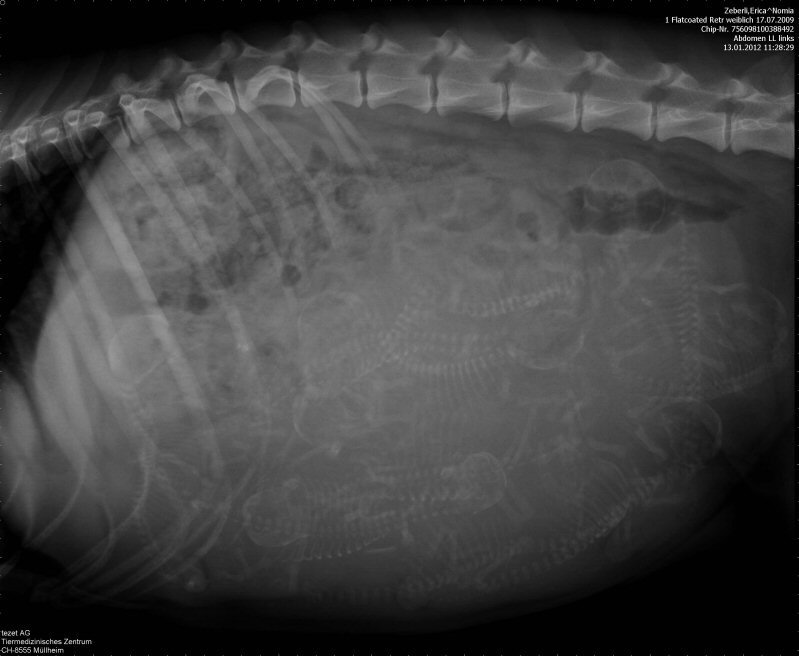

Freitag 13. Januar 2012

Nomia und Dublin haben ganze Arbeit geleistet - wir haben im Röntgenbild eine ganze Fussballmannschaft ausmachen können!

Sie ist seit heute Nachmittag bei mir und kann sich so in aller Ruhe auf die bevorstehende Geburt der 11 Welpen vorbereiten.